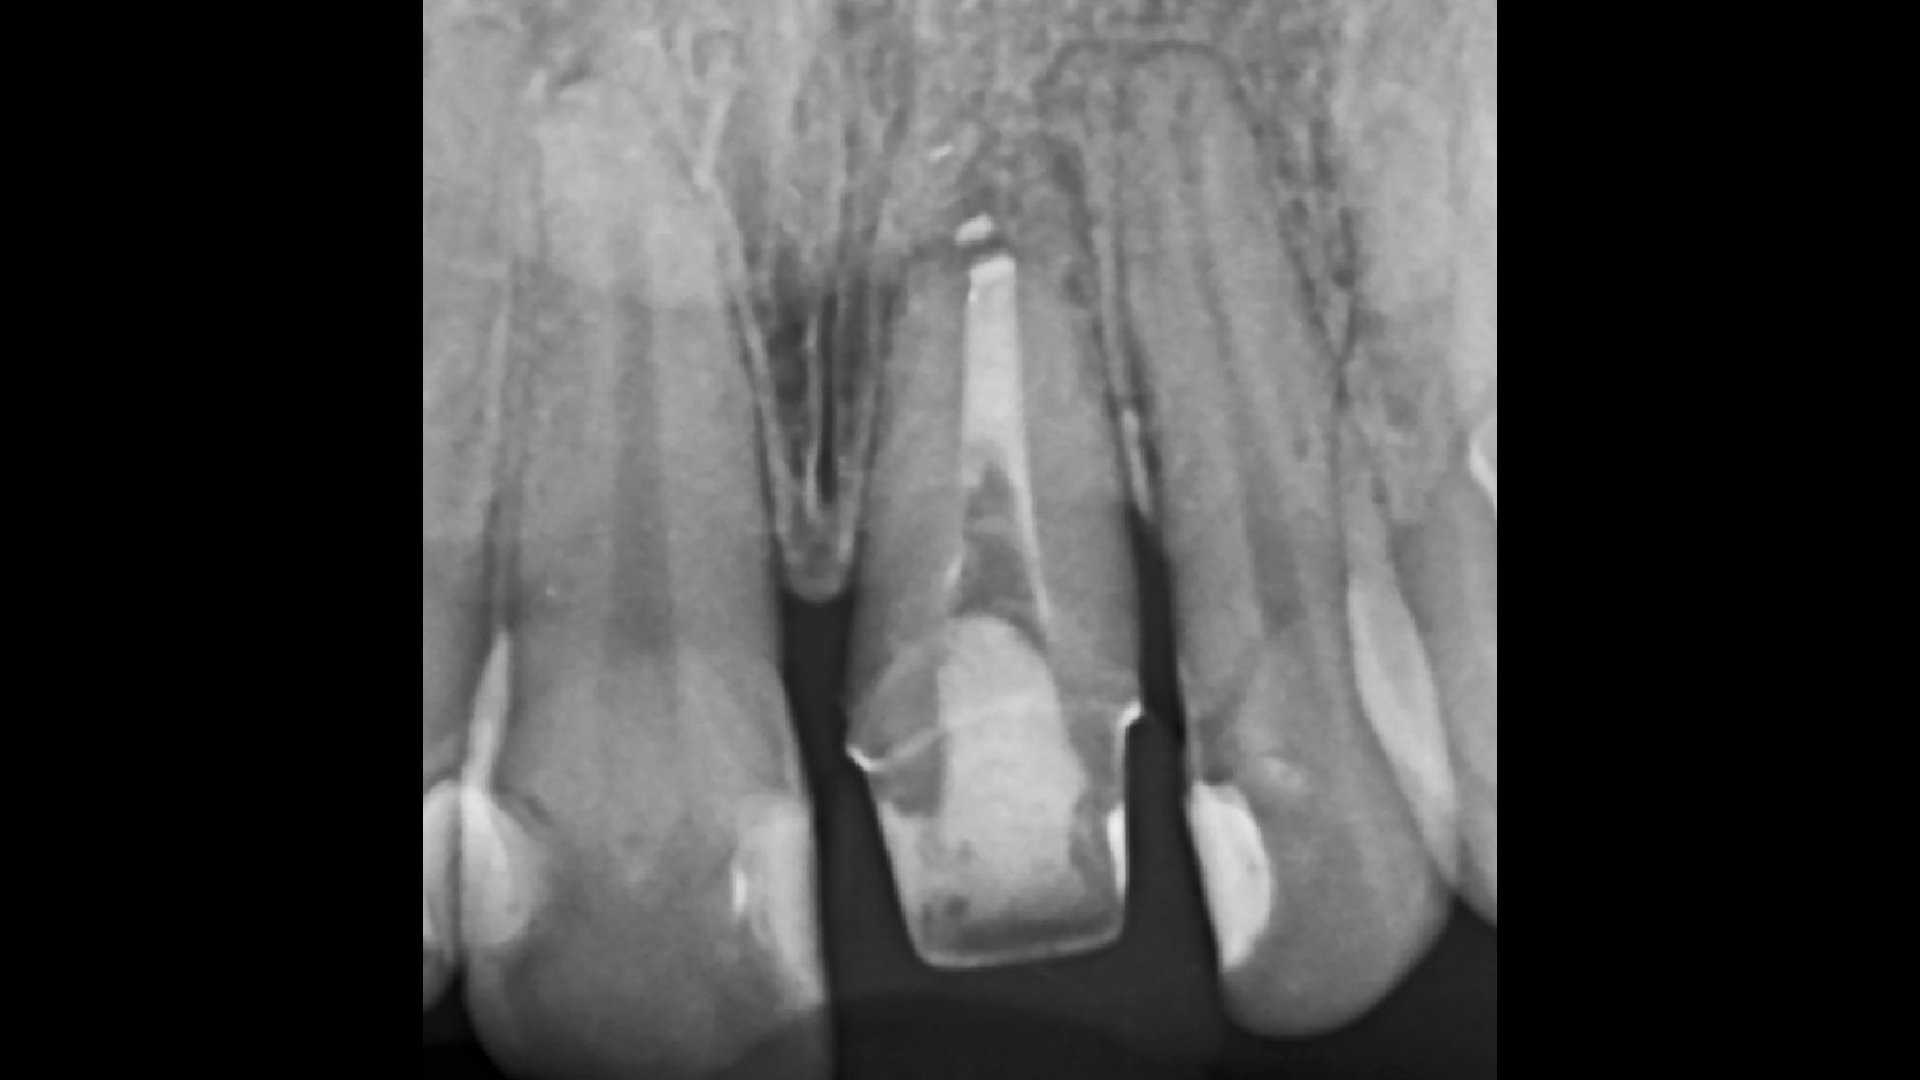

Mihaela a ajuns la noi cu plombe foarte vechi, uzate și cu discolorații, dar și cu o fațetă pe unul din dinții frontali, care nu arăta deloc bine. Echipa noastră i-a refăcut plombele vechi și fațeta.

Rezultatul final ne arată cât de importată e atenția la detalii și cât de mult poate să ne schimbe un singur dinte care nu este în armonie cu restul.